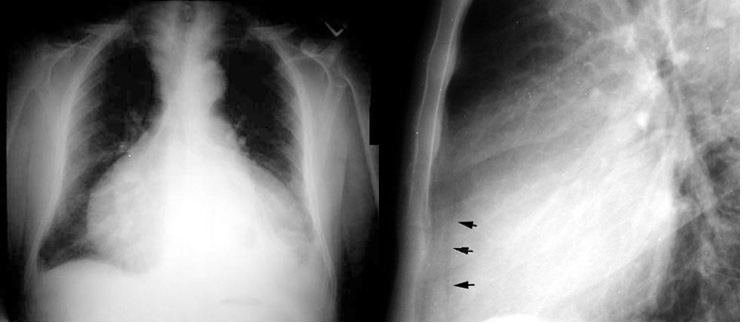

Enlarged cardiac silhouette could be pericardial effusion or cardiac enlargement. Lateral chest radiograph shows sign indicating effusion. Dorsally displaced epicardial fat pad (arrows) indicates that the cardiac silhouette is due to pericardial effusion.